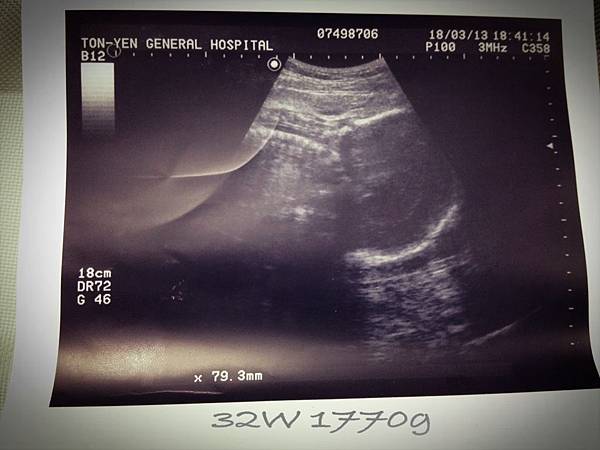

• 4月 11 週四 201316:55

• 【媽咪日記】-來到32週

32w

2013/03/18 Mon.(一)

一個月過去,又是要跟小妞見面的時候了,

肚子是一天比一天圓滾,也開始感覺往下沉了,

(繼續閱讀...)

文章標籤

佩姬 發表在 痞客邦 留言(0) 人氣(110)

• 個人分類:↖【幸せ】媽咪日記

▲top